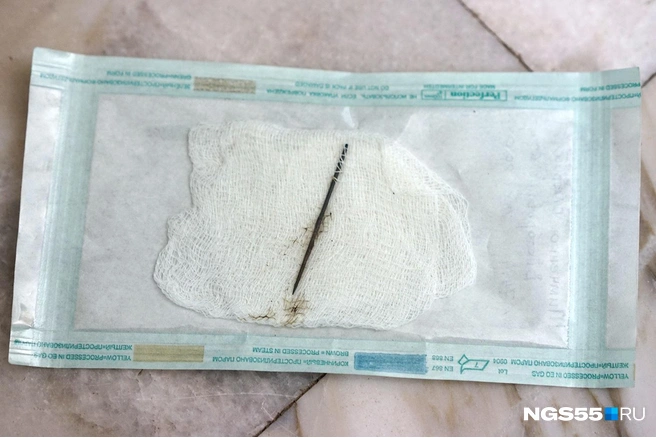

Такая история — и подобных у врачей отделения торакальной хирургии целая коробка. Свои находки они называют музеем инородных тел. Собрание, правда, неполное: часть изымают полиция и следком.

Врачи извлекают из лёгких много интересного. Из более-менее предсказуемого — ножи, пульки от воздушек и картечь от дробовиков, арматура... Всё это никогда не извлекают из пострадавших на месте, а бинтуют поверху и в таком виде доставляют хирургам.

Большую часть предметов, ставших орудиями человеческой жестокости, забирают силовики, но многое остаётся — людей с ножом в грудной клетке возят через день. Всякие есть — самодельные и заводские, металлические и керамические. Но все с застолий и с кровью.

Отдельная история — куриные кости, свечки от торта, чайные ложки... Попадался даже блистер от таблеток. Благополучно, как тот зуб, извлекаются не всегда — часто всё-таки приходится резать, если крупный предмет зашёл слишком далеко.

К жестоким, нелепым и трагичным историям хирурги привычны — хотя пациенты время от времени всё равно умудряются их удивлять. Потому врачи и держат в ординаторской свою коробку.